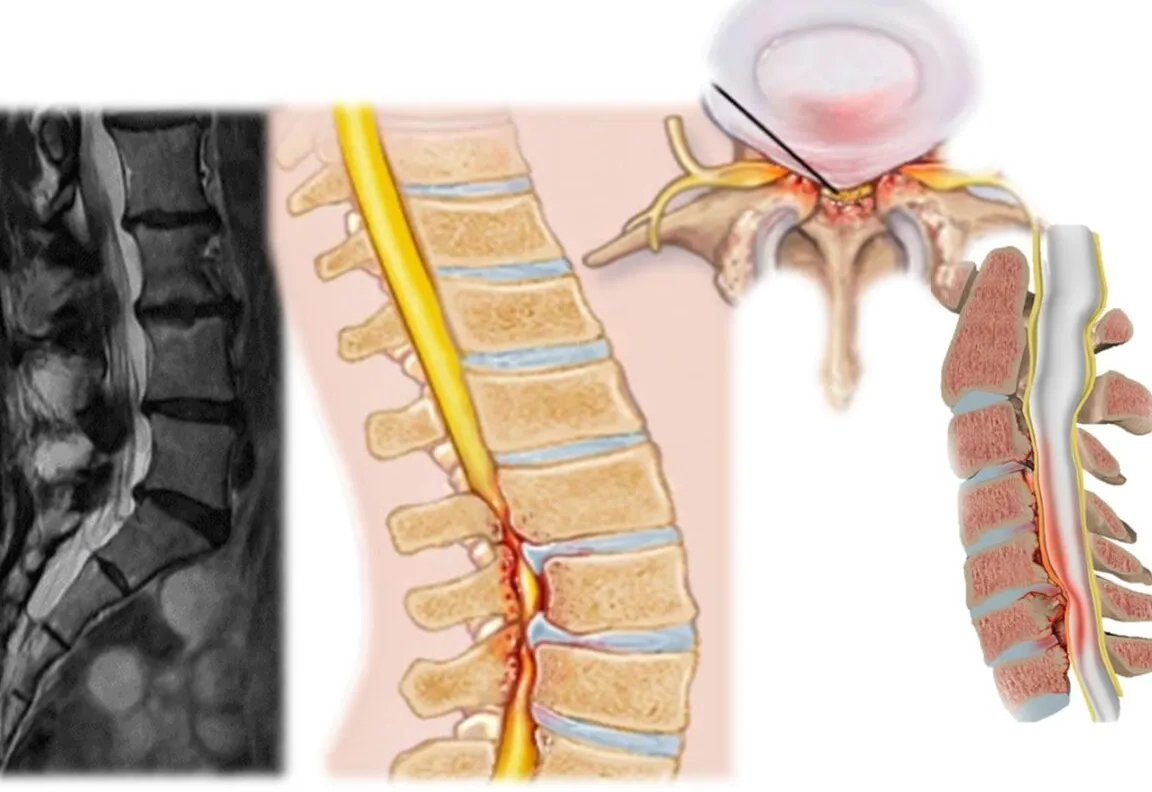

Resumen Visual de Estenosis de la Arteria Vertebral

La estenosis de la arteria vertebral es una condición donde la arteria vertebral, que pasa por las vértebras cervicales y suministra sangre al cerebro, se estrecha debido a compresión muscular, cambios degenerativos o placas, afectando las arterias vertebrales bilaterales.

Los síntomas principales incluyen mareos (arteria vertebral mareos), vértigos, dolores de cabeza, pérdida de sensibilidad en labios o encías, y en casos graves, inestabilidad de la marcha o visión borrosa, especialmente si involucra la arteria vertebral izquierda obstruida.